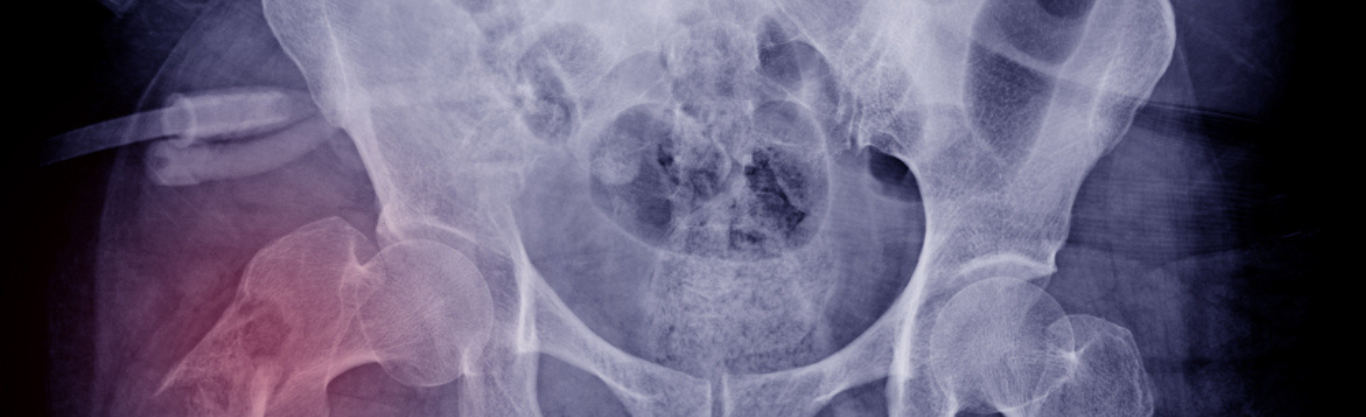

L’osteoporosi è una malattia dell’apparato scheletrico caratterizzata da una riduzione della densità minerale ossea e da un’alterazione della microarchitettura del tessuto osseo, che provocano un aumento della fragilità e, di conseguenza, un aumento del rischio di fratture, anche a seguito di traumi lievi.

Negli adulti in buona salute, i due processi sono in equilibrio e lo scheletro si mantiene stabile. Quando questo equilibrio si altera, il processo di deposizione di nuovo tessuto osseo non riesce a compensare quello di riassorbimento, per cui l’osso perde la sua compattezza e robustezza, e diventa più fragile, fino a diventare osteoporotico. Come risultato, l’osso può rompersi facilmente anche dopo una caduta di poco conto o anche con uno starnuto.

Si calcola che fino a una donna su tre e un uomo su cinque dopo i 50 anni andrà incontro a una frattura causata dall’osteoporosi, detta frattura da fragilità, e si calcola che, nel mondo, ogni 3 secondi un osso si spezzi a causa dell’osteoporosi.

Dal momento che l’osteoporosi è una malattia silenziosa e per lo più asintomatica, che spesso si manifesta per la prima volta e improvvisamente con una frattura: la radiografia realizzata per la verifica del danno può già evidenziare la presenza di osteoporosi, ma è necessario in questo caso, e comunque in presenza di fattori di rischio (prima di tutto menopausa ed età avanzata), procedere con:

- MOC Dexa che rappresenta l’esame di riferimento per la diagnosi e permette di misurare esattamente la densità minerale ossea (Bone Mineral Density, BMD), cioè la quantità (espressa in g/m2) di minerali presenti nello scheletro in toto o in alcuni distretti scheletrici particolarmente soggetti alla perdita di massa ossea. La misurazione si esegue di solito a livello della colonna vertebrale (in sede lombare), del femore o del polso. La scelta del segmento da studiare dipende da diversi fattori, tra cui il sesso e l’età del paziente: in genere, si preferisce analizzare la colonna lombare nelle donne fino a 60 anni e negli uomini fino a 65, e il collo del femore nelle persone più anziane e/o in presenza di malattie della colonna lombare.